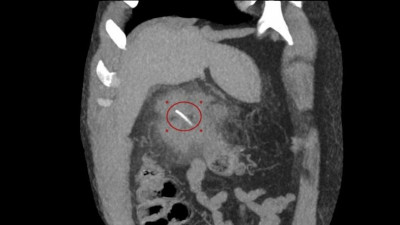

В Луховицкой больнице врачи оказали экстренную помощь 64-летнему мужчине, у которого была повреждена стенка кишечника рыбьей костью.